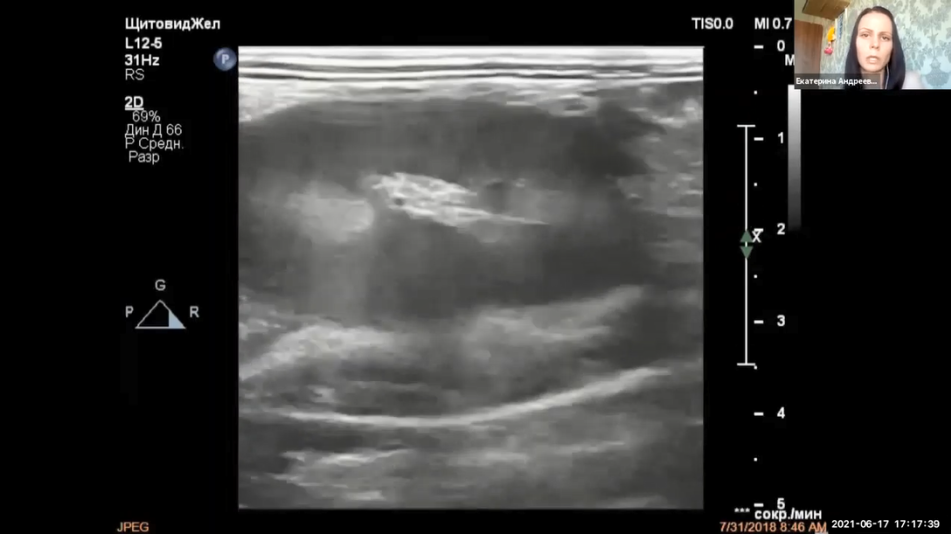

Еще одним клиническим случаем поделится доктор Андреева Екатерина Аркадьевна. Кот Мэтью (9 лет), со слов владельца начал сильно худеть, аппетит снижен и при осмотре замечен резкий уремический запах из ротовой полости. При сборе анамнеза выяснили, что кот свободного выгула и имеет контакт с другими котами.